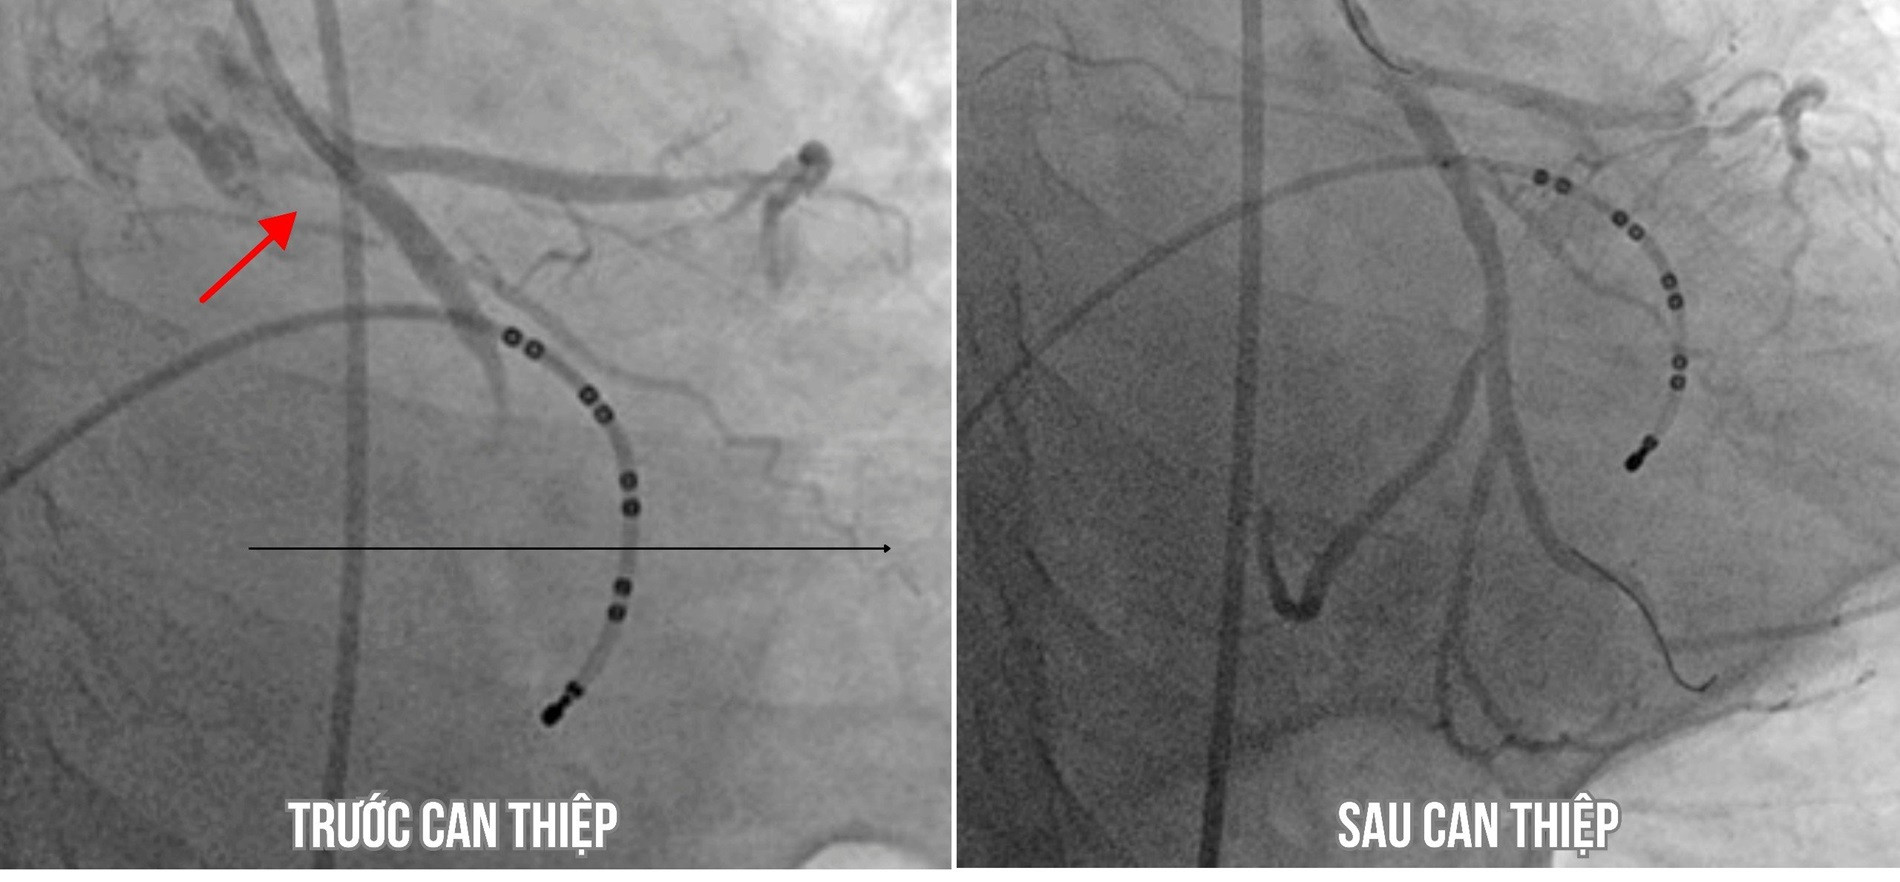

Kết quả chụp mạch vành cho thấy, bà H. bị tắc hoàn toàn động mạch mũ, hẹp 90% động mạch liên thất trước. Bệnh nhân được hút huyết khối, nong bóng và đặt stent tại vị trí mạch vành bị tắc.